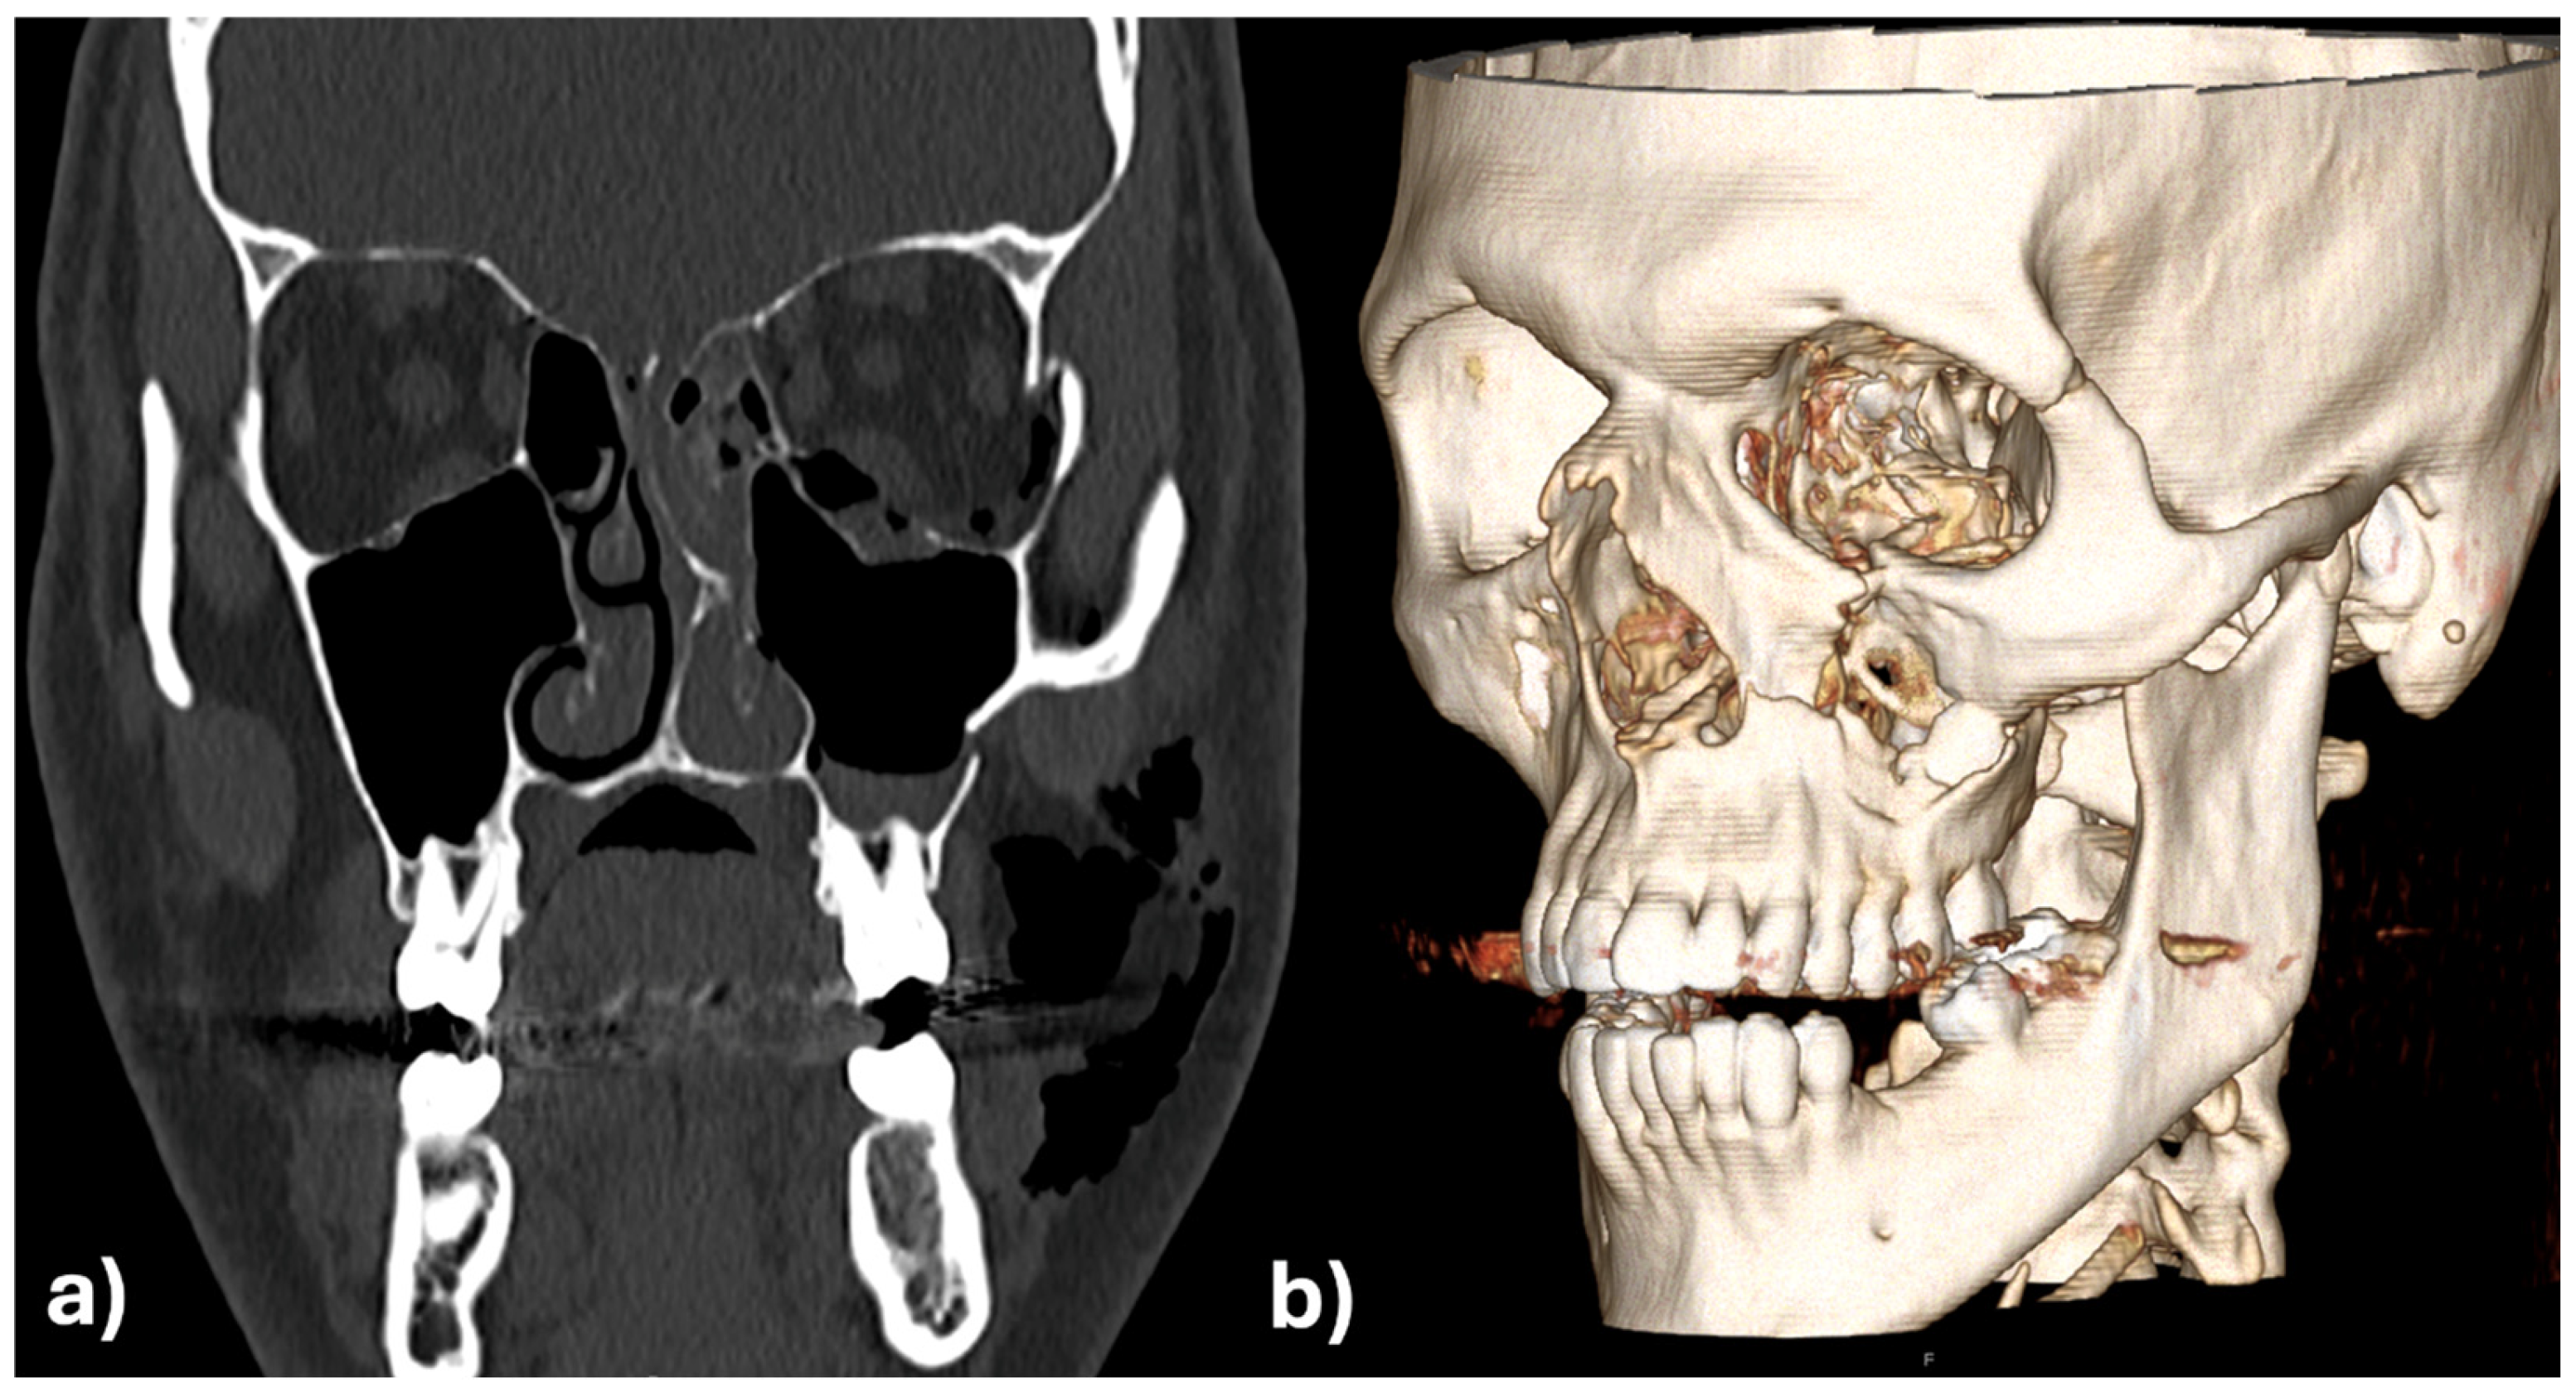

Figure 10a,b are showing the images of the intraoperative 3D C-arm scan and Figure 11 shows the image fusion between plan and achieved result.

Figure 10. 3D (a) and in coronal view (b) of the intraoperative 3D scan which shows an almost perfect anatomic reconstruction and fit of the patient specific implants.